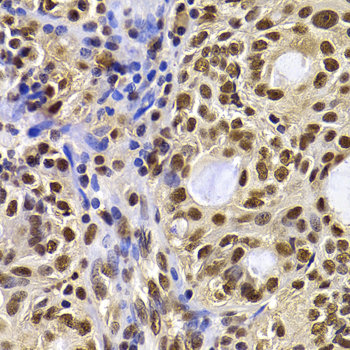

Immunohistochemistry - HIRIP3 Polyclonal Antibody

Immunohistochemistry of paraffin-embedded human oophoroma using HIRIP3 antibody at dilution of 1:100 (40x lens).